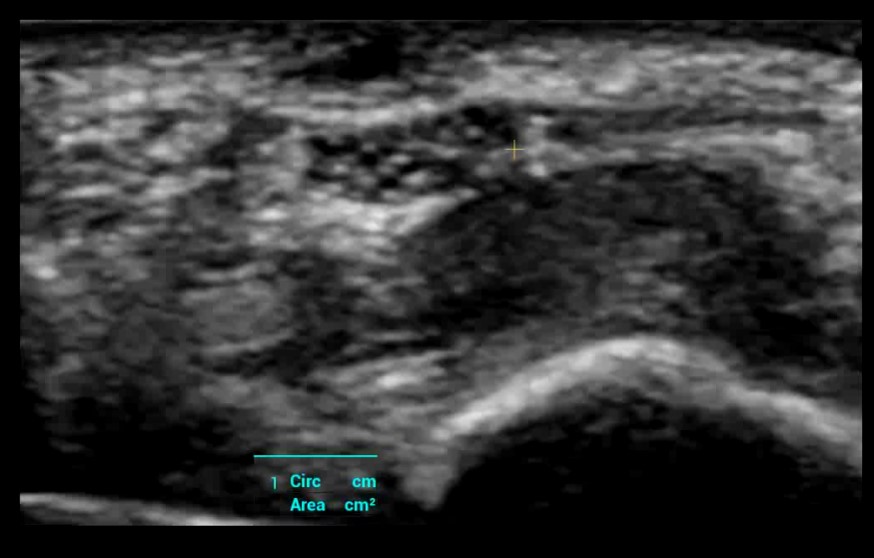

Smart Breast - Auto protokol na skenovanie prsníkov a analýza BI-RADS

Smart Thyroid - Inteligentný protokol štítnej žľazy + analýza TI-RADS

Smart Trace: Automatické a presné ohraničenie lézie a ich pomeranie.

HiFR STE Elastography: Kompletná a výkonná elastografia. Shear Wave Elastografia (HiFR STE, STQ). Strain - Natural Touch Elastografia (NTE). Vysoká citlivosť, penetrácia a presnosť. Unikátna “shell” analýza hodnotiaca infiltráciu tumoru do okolia. Automatické ohraničenie ložiska a shear wave kvantifikácia tuhosti tkaniva. Presné posúdenie tuhosti tkaniva pomôže v diagnostickom odlíšení malígneho a benígneho nálezu.

Smart Trace: Automatické a presné ohraničenie lézie a ich pomeranie.

HiFR STE Elastography: Kompletná a výkonná elastografia. Shear Wave Elastografia (HiFR STE, STQ). Strain - Natural Touch Elastografia (NTE). Vysoká citlivosť, penetrácia a presnosť. Unikátna “shell” analýza hodnotiaca infiltráciu tumoru do okolia. Automatické ohraničenie ložiska a shear wave kvantifikácia tuhosti tkaniva. Presné posúdenie tuhosti tkaniva pomôže v diagnostickom odlíšení malígneho a benígneho nálezu.

Smart Brads – software umelej inteligencie: Automatické vyhľadanie lézie a jej ohraničenie. Štandardizovaný protokol detekcie lézií v oboch rovinách. Automatická B-RADS analýza. Presná a plne automatická detekcia lézií s obkreslením a pomeraním, B-RADS analýzam a vytvorenie report. Urobí vaše klinické rutinné UZV skenovanie prsníka PRESNEJŠIE, RÝCHLEJŠIE a JEDNODUCHŠIE.

Smart Breast - Auto protokol na skenovanie prsníkov a analýza BI-RADS